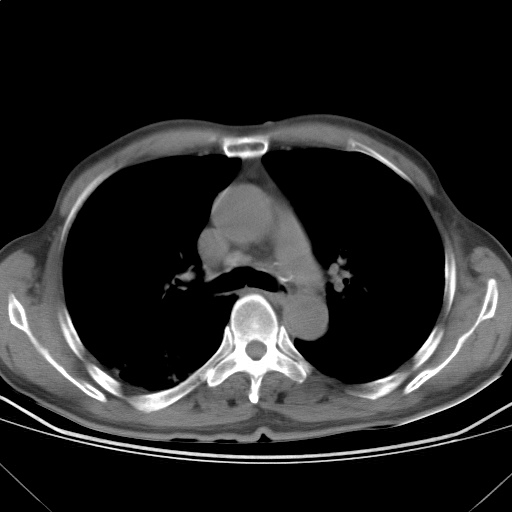

以下是引用随光逐影在2009-5-1 13:53:00的发言:[br]考虑为:1)两肺血行播散型肺结核;2)右肺下叶炎症感染。3)右侧胸膜增厚。